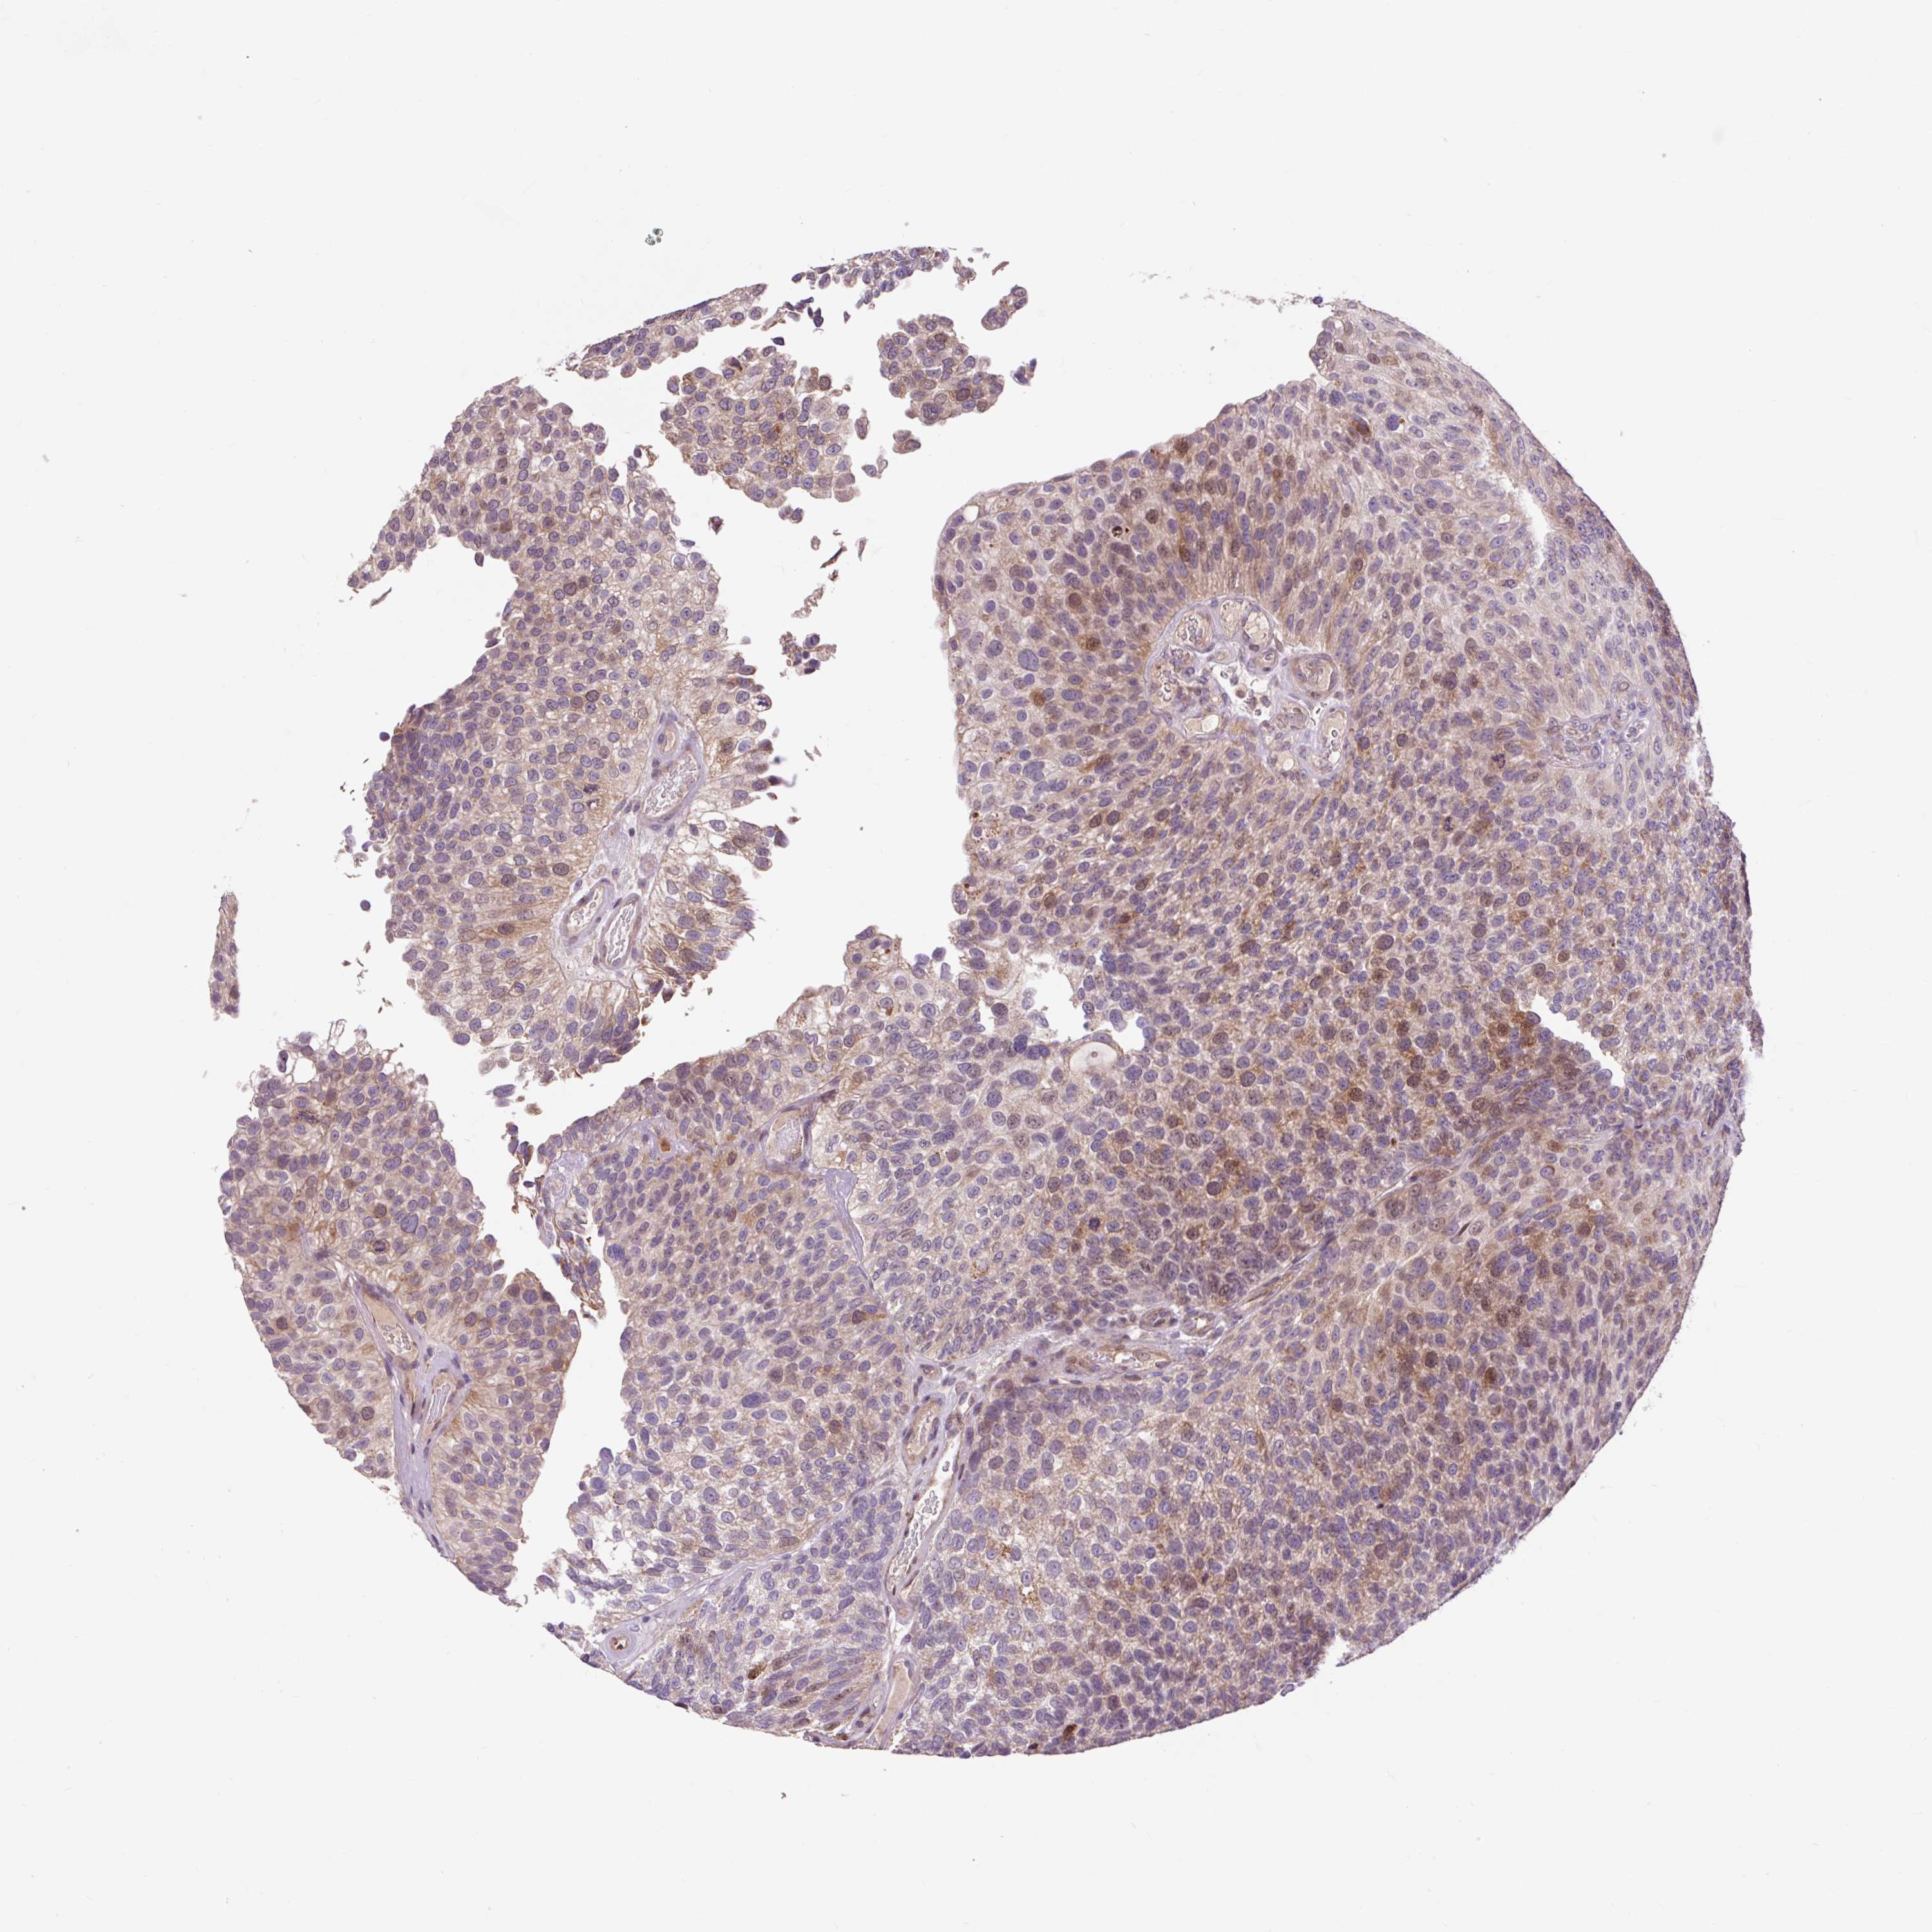

UROTHELIAL CANCER - Protein expressioni

A mouse-over function shows sample information and annotation data. Click on an image to view it in a full screen mode. Samples can be filtered based on level of antibody staining by selecting one or several of the following categories: high, medium, low and not detected. The assay and annotation is described here.

Note that samples used for immunohistochemistry by the Human Protein Atlas do not correspond to samples in the TCGA dataset.

Antibody stainingi

Antibody staining in the annotated cell types in the current human tissue is reported as not detected, low, medium, or high, based on conventional immunohistochemistry profiling in selected tissues. This score is based on the combination of the staining intensity and fraction of stained cells.

Each image is clickable and will lead to virtual microscopy that enables deeper exploration of all samples and also displays staining intensity scores, fraction scores and subcellular localization as well as patient and tissue information for each sample.

Antibody HPA054372

Staining

High

Medium

Low

Not detected

Intensity

Strong

Moderate

Weak

Negative

Quantity

>75%

75%-25%

<25%

None

Location

Nuclear

Cytoplasmic/membranous

Cytoplasmic/membranous,nuclear

Urothelial carcinoma, High grade

Urothelial carcinoma, NOS

Urothelial carcinoma, Low grade